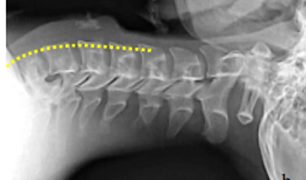

For the diagnosis, in addition to the symptoms, a radiographic study is performed. When it comes to radiopaque foreign bodies located in the cervical portion, they are identified with a simple lateral neck radiograph (Image 1) and when they are found in the thoracic portion, posteroanterior, lateral, or oblique simple chest radiographs are performed (Image 2). These same radiographs show evidence of non-opaque foreign bodies in the esophagus in the form of an increase in the distance between the cervical vertebrae and the larynx or trachea, or by the presence of air inside the esophagus. If nothing is found in this way, a contrast study of the esophagus should be performed, using a small cotton swab saturated with a suspension of barium sulfate or a water-soluble radiopaque solution, The same radiographic views are made and the stoppage of the swab inside the esophagus is observed (Images 3) (Image 4). Frequently, the patient continues to have the sensation that the foreign body persists despite the lack of radiographic evidence that this is the case. In these cases, the possibility of the presence of a foreign body must be excluded by esophagoscopy after the first 24 hours.15–18

Figure 1 The proximal esophagus follows the lordosis of the cervical and thoracic spine; keep the cervical spine in a straight line with the thoracic spine elevating the head.